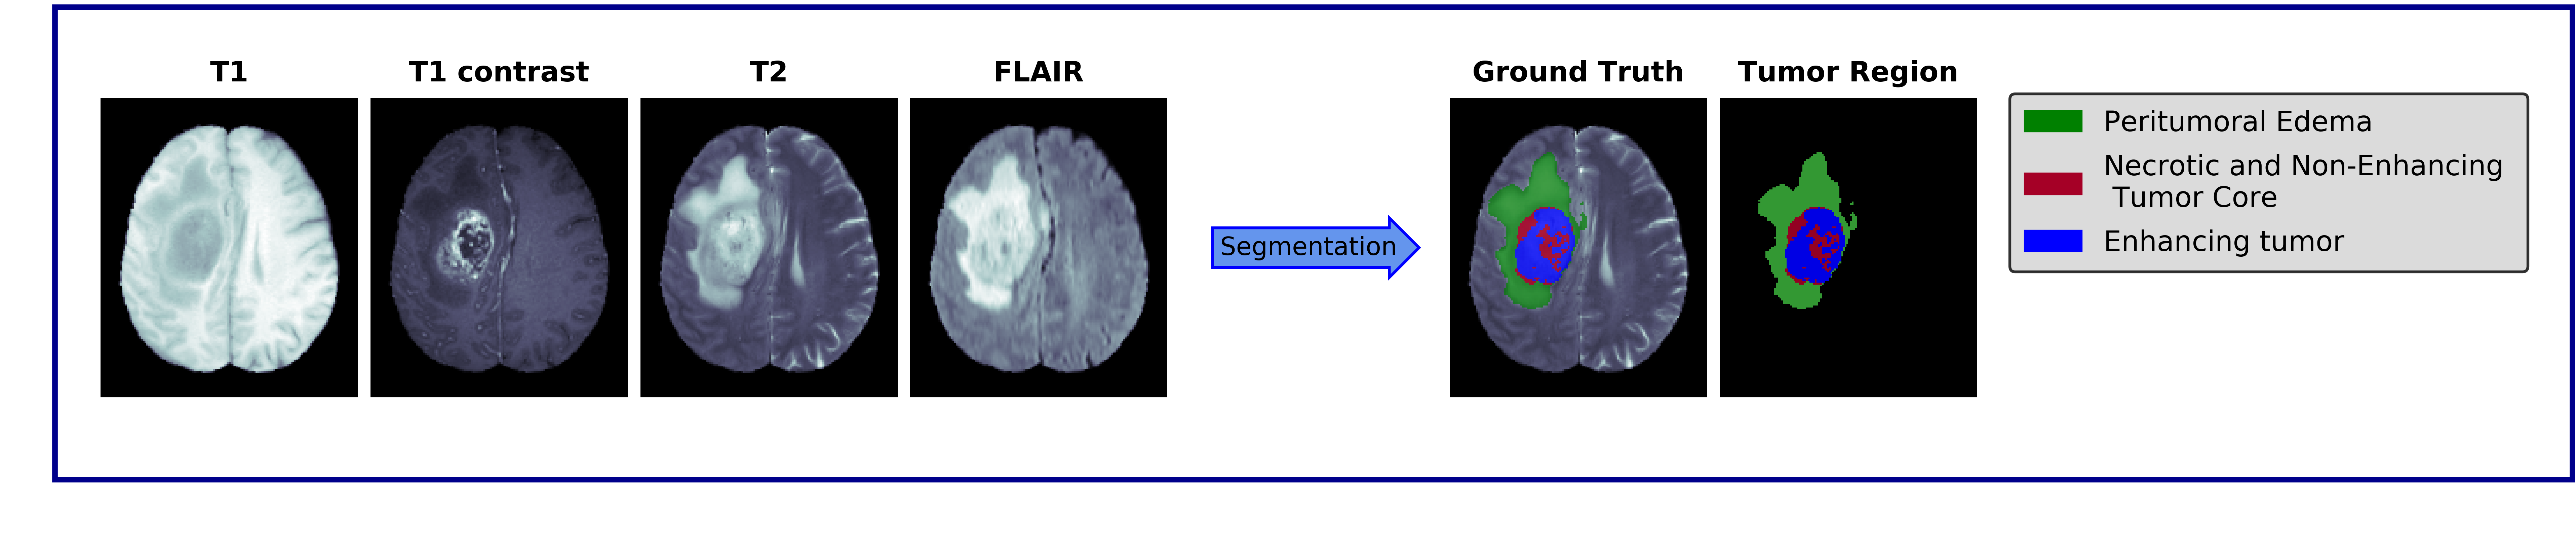

Clinical diagnostic and treatment decisions rely upon the integration of patient-specific data with clinical reasoning. Cancer presents a unique context that influence treatment decisions, given its diverse forms of disease evolution. Biomedical imaging allows noninvasive assessment of disease based on visual evaluations leading to better clinical outcome prediction and therapeutic planning. Early methods of brain cancer characterization predominantly relied upon statistical modeling of neuroimaging data. Driven by the breakthroughs in computer vision, deep learning became the de facto standard in the domain of medical imaging. Integrated statistical and deep learning methods have recently emerged as a new direction in the automation of the medical practice unifying multi-disciplinary knowledge in medicine, statistics, and artificial intelligence. In this study, we critically review major statistical and deep learning models and their applications in brain imaging research with a focus on MRI-based brain tumor segmentation. The results do highlight that model-driven classical statistics and data-driven deep learning is a potent combination for developing automated systems in clinical oncology.